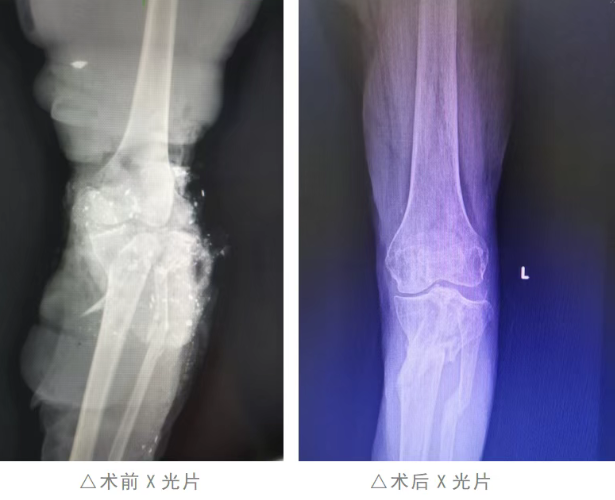

彼时,农历乙巳年腊月的寒意正浓,年味渐浓的街巷里满是迎接新春的期盼,谁也未曾想到,一场致命危机正悄然降临。2024年12月30日,一阵急促的急救鸣笛声划破院区的宁静,一辆大货车碾压致重伤的李某某被紧急送至我院急诊。61岁的她,处于严重休克状态,左下肢从踝关节往上3cm至大腿根部皮肤全层脱套,左中下腹部皮肤同样受损,左膝关节更是遭遇完全性开放性粉碎性骨折,创面血肉模糊,生命体征微弱如风中残烛。

手术台上,医护人员凝神聚力、默契配合,精准处理创面、修复损伤组织,每一个动作都承载着生命的重量;手术台下,各科室全程待命,随时应对突发状况。历经数小时的奋战,手术顺利完成,患者被安全转回重症二区继续监护。然而,救治之路并未就此平坦,休克、感染、弥漫性血管内凝血等多重难关接踵而至,多科室医护人员日夜坚守、精准施策,一次次将患者从死亡边缘拉回,在众人的合力守护下,患者病情逐渐趋于稳定,顺利转入骨科中心—创伤骨科接受后续治疗。

术后恢复阶段,新的挑战再度出现——患者下肢出现大面积皮肤坏死。骨科中心—创伤骨科医师团队迅速开展全员会诊,结合患者身体状况制定个性化治疗方案,决定在彻底清创后实施大面积邮票植皮手术。术后,护理团队精心照料,密切监测植皮生长情况,日复一日的细致呵护换来了回报,植皮区域长势良好,为后续康复奠定了坚实基础。

植皮成功与骨折固定虽稳住了病情,却因长期固定导致患者膝关节僵硬,无法正常活动。为帮助患者恢复肢体功能,骨科中心—创伤骨科第一时间邀请康复科会诊,经多学科研讨后,将患者转至康复科进行针对性康复训练。三个月里,康复科医师为患者量身定制训练计划,从被动活动到主动锻炼,循序渐进引导患者恢复膝关节功能,每一点进步都凝聚着医患双方的坚持与努力,最终实现了膝关节从僵硬固定到屈伸40度的突破性进展。